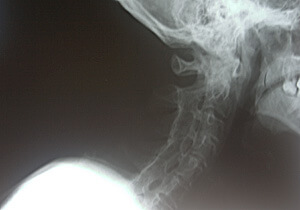

39 year old male came in today with chief complaint of not being able to move his neck. Patient was diagnosed with Ankylosing spondylitis in his 20s. Up to a year ago, although his range of motion was compromised but still he was able to move the neck somewhat , however since then his range of motion has been getting worse, at this point he can not move the neck at all; cervical range of motion=0 degree in all axis. He is other wise a healthy male. He takes no medications and he receives regular chiropractic treatments. He is working and is productive, and he has noted eating vegetables helps his condition.

Discussion: Ankylosing spondylitis is an auto-immune entity that can cause inflammation of the entire spine and the sacroiliac joints. The chronic inflammation here can cause pain and stiffness, in the long term the spondylitis (medical lingo: spinal inflammation ) can lead to a complete fusion of spine. Ankylosing spondylitis is much more common in males than in females. (in fact I have not seen it in females as of yet) Most commonly striking patients in their 20s and 30s. It is felt that the problem is genetic, and there is a specific blood test for it known as HLA-B27. The symptoms are typically pain and stiffness in lower back, upper buttock area, neck, and possibly the rest of the spine. X-rays and physical exam may show the appearance of so called bamboo spine (see picture). TNF blockers (Enbrel, Humira and Remecade) may play a role.